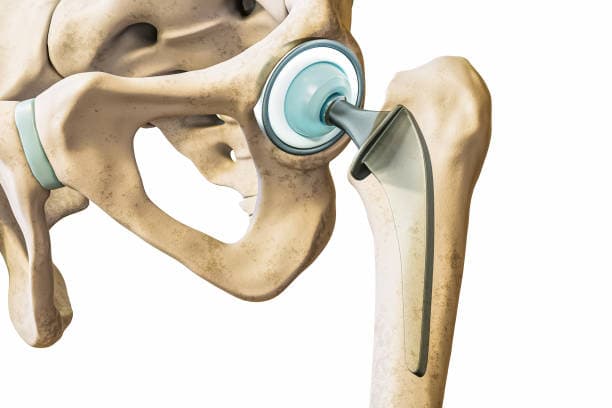

The surgical procedure involves making an incision over the hip, through which the surgeon accesses the joint. The damaged femoral head is removed and replaced with a metal or ceramic ball attached to a stem that fits into the femur. The acetabulum is also prepared by removing any damaged cartilage and bone, then resurfaced with a metal or plastic cup. These prosthetic components are designed to mimic the natural anatomy and movement of the hip joint, allowing for smooth articulation and reduced pain.

Removal of Damaged Tissue: The next step involves removing the damaged portions of the hip joint. The femoral head (the ball of the joint) is dislocated from the acetabulum (the socket) and then cut off using specialized surgical instruments. Any damaged cartilage and bone in the acetabulum are also removed and prepared for the new implant.

Implant Placement: The prepared bone surfaces are fitted with the prosthetic components. The femoral component, which includes a metal stem and a ball, is inserted into the femur. This can be cemented in place or designed to allow bone growth into the implant. The acetabular component, typically a metal shell with a plastic or ceramic liner, is placed into the prepared socket. These components are aligned to ensure proper joint movement and stability.